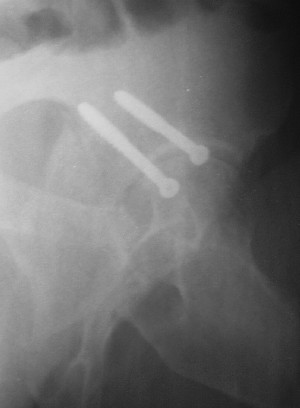

19/05/03

При поступлении в госпиталь 3.06.03

Больной 18 мая 2003 года в автоаварии получил перелом левой вертлужной впадины, вывих бедра. Госпитализирован в один из стационаров области.Вывих вправлен. В последствии бедро вывихивалось еще дважды. На консультацию был представлен снимок от 19.05.03г., больной переведен к нам 3.06.03г. Снимок при поступлении - перелом впадины, задне-верхний вывих бедра. 05.06.2003 г. выполнено открытое вправление вывиха левого бедра и остеосинтез стенки вертлужной впадины двумя винтами. Послеоперационный период без осложнений. Объем движений в левом тазобедренном суставе восстановился полностью. Выписан на амбулаторное лечение в удовлетворительном состоянии с рекомендациями 3 месяца ходить на костылях без нагрузки на оперированную конечность. На контрольных рентгенограммах левого тазобедренного сустава 13.10.2003 г. - признаки консолидации перелома; плотность, форма головки и состояние суставных поверхностей удовлетворительные. Разрешена дозированная осевая нагрузка, на конечность с использованием дополнительной опоры. 19.12.2003 г. больной обратился с жалобами на боли в левом тазобедренном суставе. На рентгенограммах левого тазобедренного сустава 19.12.2003 г., 20.02.04г. - асептичекий некроз головки бедра. 5.04.04г. - эндопротез. Сейчас ходит без трости, не хромает. Особенность эндопротезирования - при удалении винтов прослежена линия перелома заднего края впадины и предложено установить чашку несколько меньшего диаметра, чтобы она была покрыта несломанной частью.